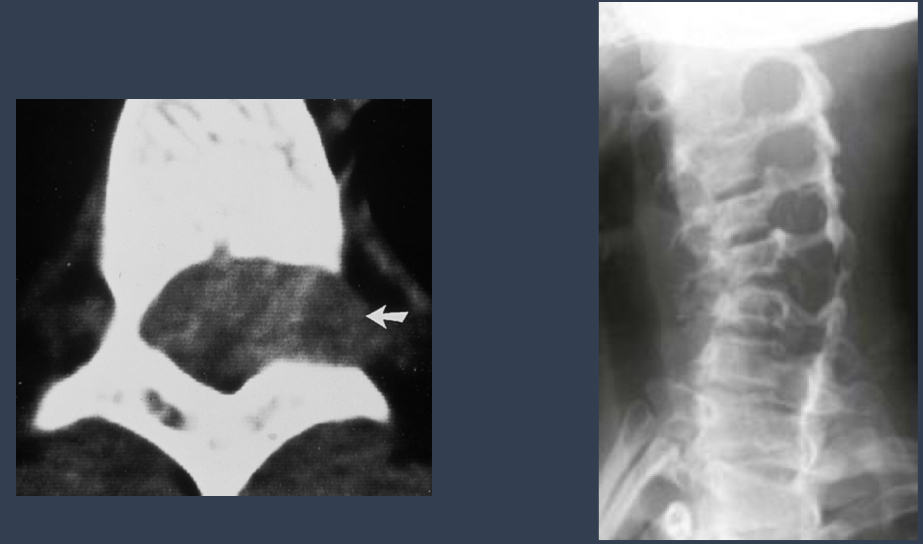

what is this?

enlarged IVF

neurofibromatosis